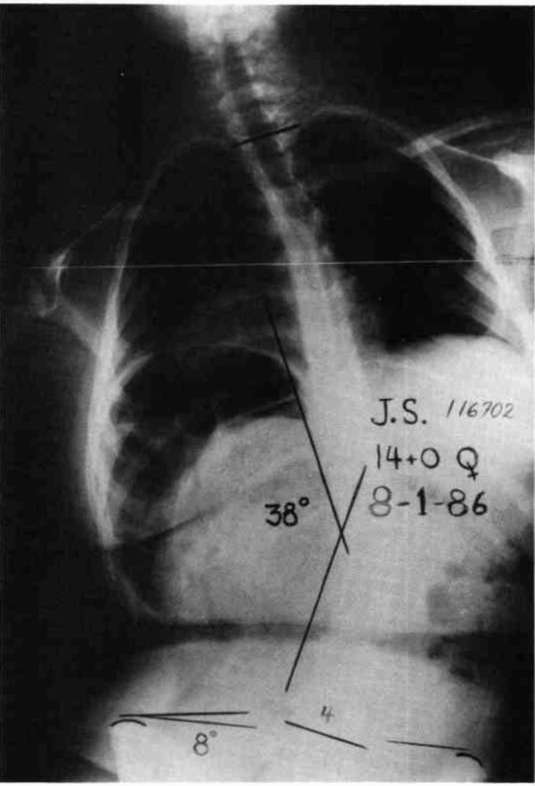

Let us now look at two examples were these stabilizing schemes have been simultaneously applied. Fig. 10a is a photo of a 12 year old boy with muscular dystrophy, sitting as he was presented to us. Fig. 10b shows the sitting support system properly applied. The corset is entirely independent; it is not attached to the seat. Fig. 10c and Fig. 10d compare his A-P spine x-rays without and with the orthotic system. The lateral tilt of his pelvis is reduced from 30 degrees to 14 degrees. The Cobb angle of his scoliosis was reduced from 65 degrees to 35 degrees. Curve control of this magnitude is not unusual as long as the deformity is still flexible. Fig. 11a is the x-ray of J.S., a 14 year old girl with cerebral palsy. She presented a right thoraco-lumbar scoliosis of 38 degrees and a rightward pelvic tilt of 8 degrees. Her shoulders were tilted 13 degrees to the left partly because she used her right arm for propping to avoid falling to the right. We provided her with a soft corset and the Gillette Sitting Support Orthosis. The Sitting Support Orthosis was to provide pelvic control and bilateral "propping" support. It had no head rest or anterior support. The x-ray taken just after fitting shows pelvic tilt reduced to 2 degrees (Fig. 11b), the Cobb angle of the scoliosis reduced to 22 degrees, and shoulders leveled. Both hands were free to function, and she said she could breathe deeper.

Figure 11a. X-ray of J.S., a 14 year old girl with cerebral palsy.

Figure 11b. J.S. provided with a soft corset and the Gillette Sitting Support Orthosis.